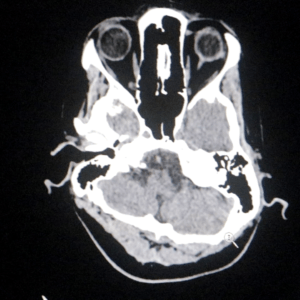

Durante el año, el servicio logró dar respuesta a un amplio abanico de patologías neurológicas de alta complejidad, incluyendo cuadros vasculares, tumorales y emergencias neuroquirúrgicas, consolidando al Parque de la Salud como centro de referencia regional.

En el área de emergentología, el servicio tuvo una fuerte intervención durante 2025, principalmente en casos de traumatismos de cráneo derivados de accidentes.